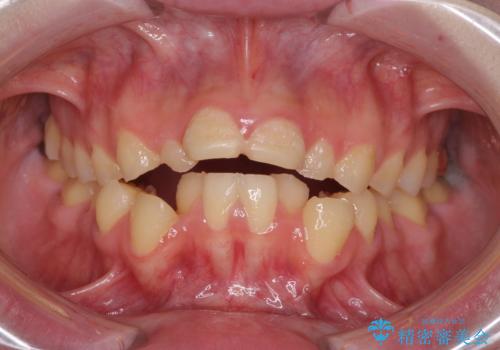

- 一時期の拒食症に伴い歯が酸で溶けてボロボロになってしまったとのことで来院された患者様です。

酸によりエナメル質の大半が溶けており、下顎前歯以外は酷いむし歯のような状態でした。